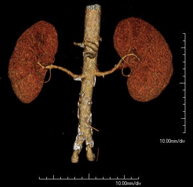

- Angio-TC arterias renales

Prueba diagnóstica no invasiva que consiste en el estudio de las arterias renales obteniendo imágenes de alta definición anatómica mediante el empleo de un equipo de TC (Tomografía Computarizada) y de contraste yodado. La calidad de las imágenes permite realizar reconstrucciones en 2D y 3D gracias a estaciones de trabajo especializadas en el estudio arterial. Esta prueba está indicada, por ejemplo, en aquellos pacientes que sufren de HTA refractaria al tratamiento, en pacientes con lesiones renales para tener un mapa "vascular" pre-quirúrgico, etc.